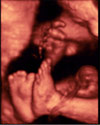

Ecografía 4D del tercer trimestre: Bebé del sexo masculino

Tiene piernas flexionadas hacia arriba

El examen ecográfico en 4D no deja lugar a dudas: se trata de un varón –vemos su aparato genital en primer plano- con las piernas flexionadas hacia arriba. El bebé se encuentra en las últimas semanas de gestación.